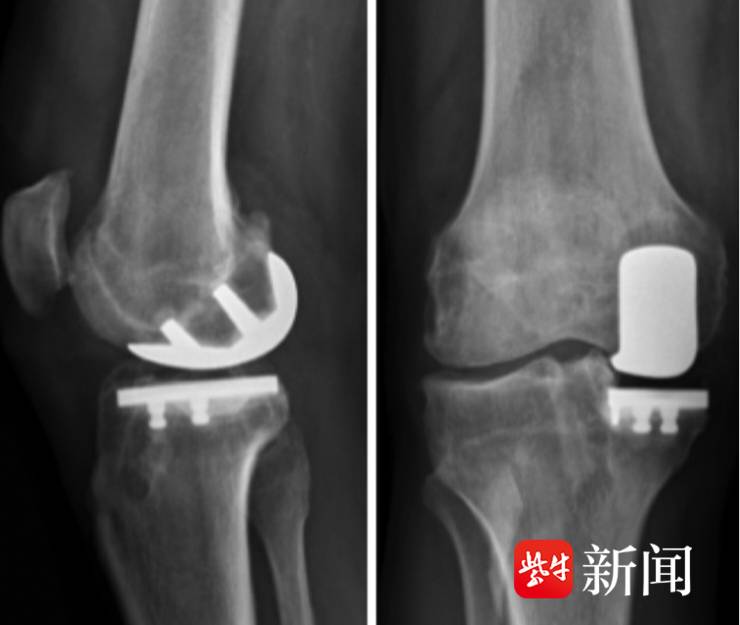

![]()

术前影像资料

术后影像资料